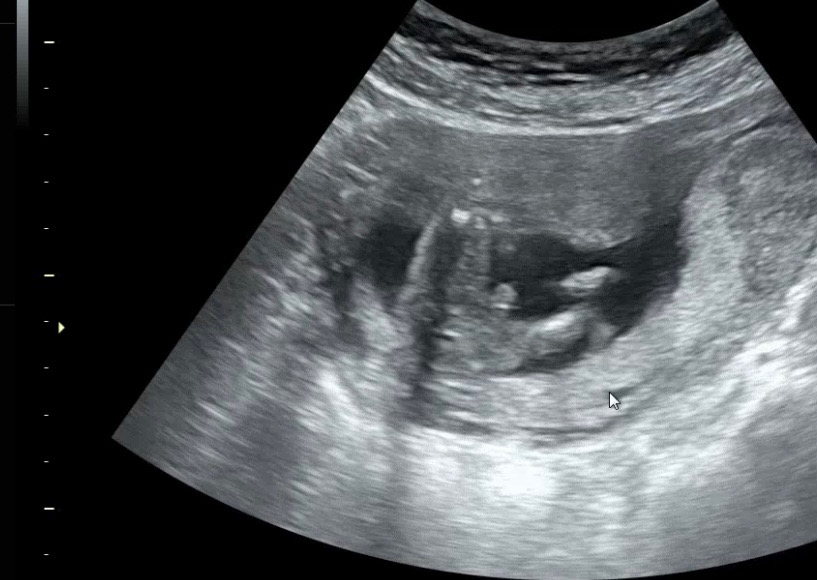

안녕하세요.16주 산모에용 오늘 초음파보고왔는데, 저는 아들같은데 맞을까요? 성별 20주까지 변할수도있을까요?

아들이네요 세상에

저정도면 반전없을꺼같아욬ㅋㅋㅋㅋㅋ너무 아들🥰

병원에서는 뭐래용 아들은 반전 거의 없어용